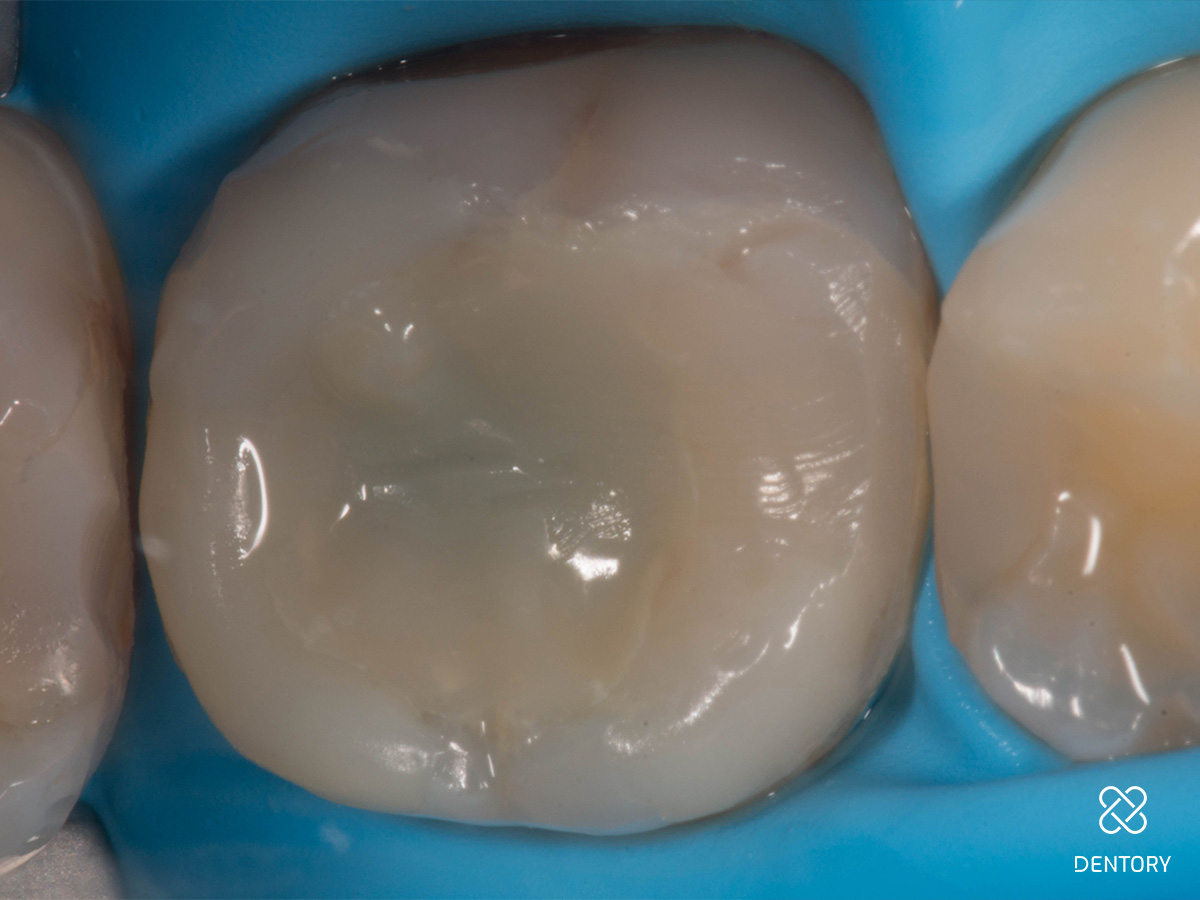

Abbildung 13

Die letzten 1,5mm wurden mit einem Komposit (A3) verschlossen und ausgearbeitet.